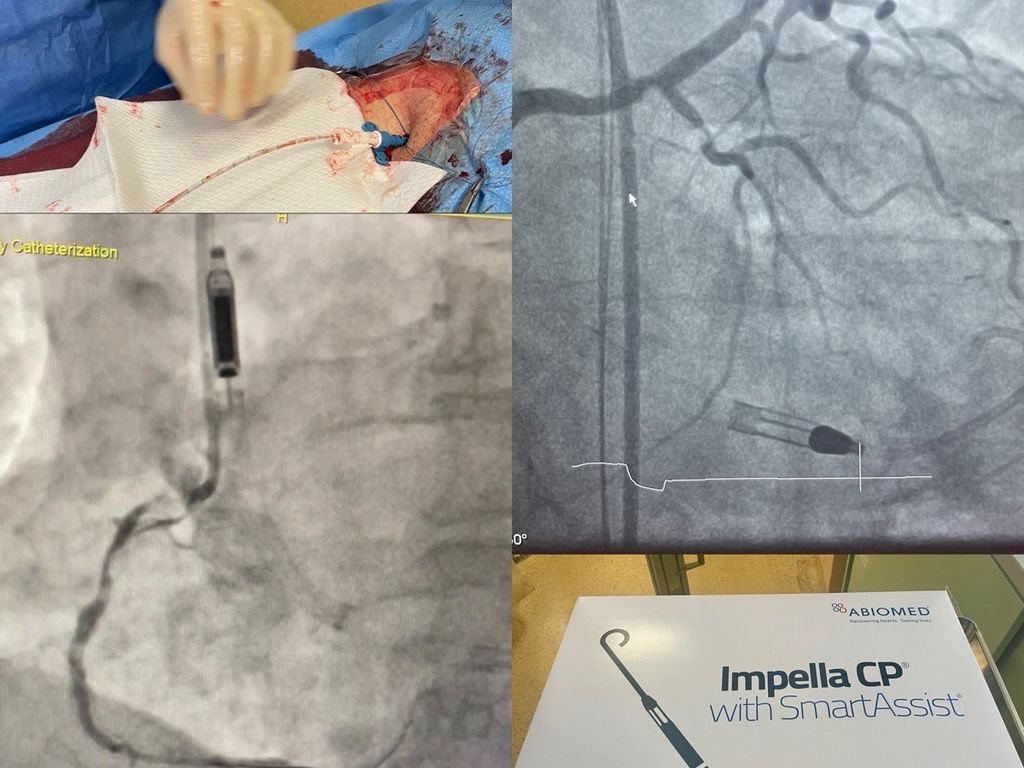

All’ospedale di Savigliano è stato portato a termine con successo un delicato intervento di rivascolarizzazione percutanea complessa con il supporto dell’Impella, un dispositivo avanzato per l’assistenza ventricolare sinistra, ovvero una pompa che viene inserita nel cuore del paziente passando tramite un’arteria femorale per garantire la circolazione ottimale del sangue anche in caso di insufficienza cardiaca.

L’intervento è stato eseguito dall’équipe composta dal direttore della struttura di Cardiologia Michele De Benedictis, con i colleghi Umberto Barbero e Mattia Doronzo recentemente entrato a far parte della struttura, e riguardava un paziente con multiple gravi stenosi coronariche e con il cuore affetto da una grave riduzione della capacità di pompare il sangue.

“Il supporto dell’Impella ci ha permesso di affrontare una situazione estremamente complessa in totale sicurezza, sostenendo la funzione cardiaca durante tutto l’intervento” spiega il dottor Barbero. Che aggiunge: “Abbiamo inoltre utilizzato un’innovativa tecnica di impianto perfezionata per ridurre al minimo l’invasivitá della puntura femorale che ha garantito al paziente sicurezza durante la procedura e tempi di recupero rapidissimi”.

De Benedictis sottolinea l’importanza di disporre di un team altamente qualificato e tecnologie all’avanguardia: “Questo intervento dimostra come la nostra struttura sia ormai un punto di riferimento per la cardiologia interventistica della Provincia. Grazie all’utilizzo di dispositivi innovativi come l’Impella, e a un team che comprende anche i cardiologi Cinzia Moncalvo e Giorgio Marengo e tutti gli infermieri e tecnici di radiologia che si alternano quotidianamente nella sala di emodinamica, possiamo garantire ai pazienti con patologie complesse un trattamento sicuro ed efficace”.